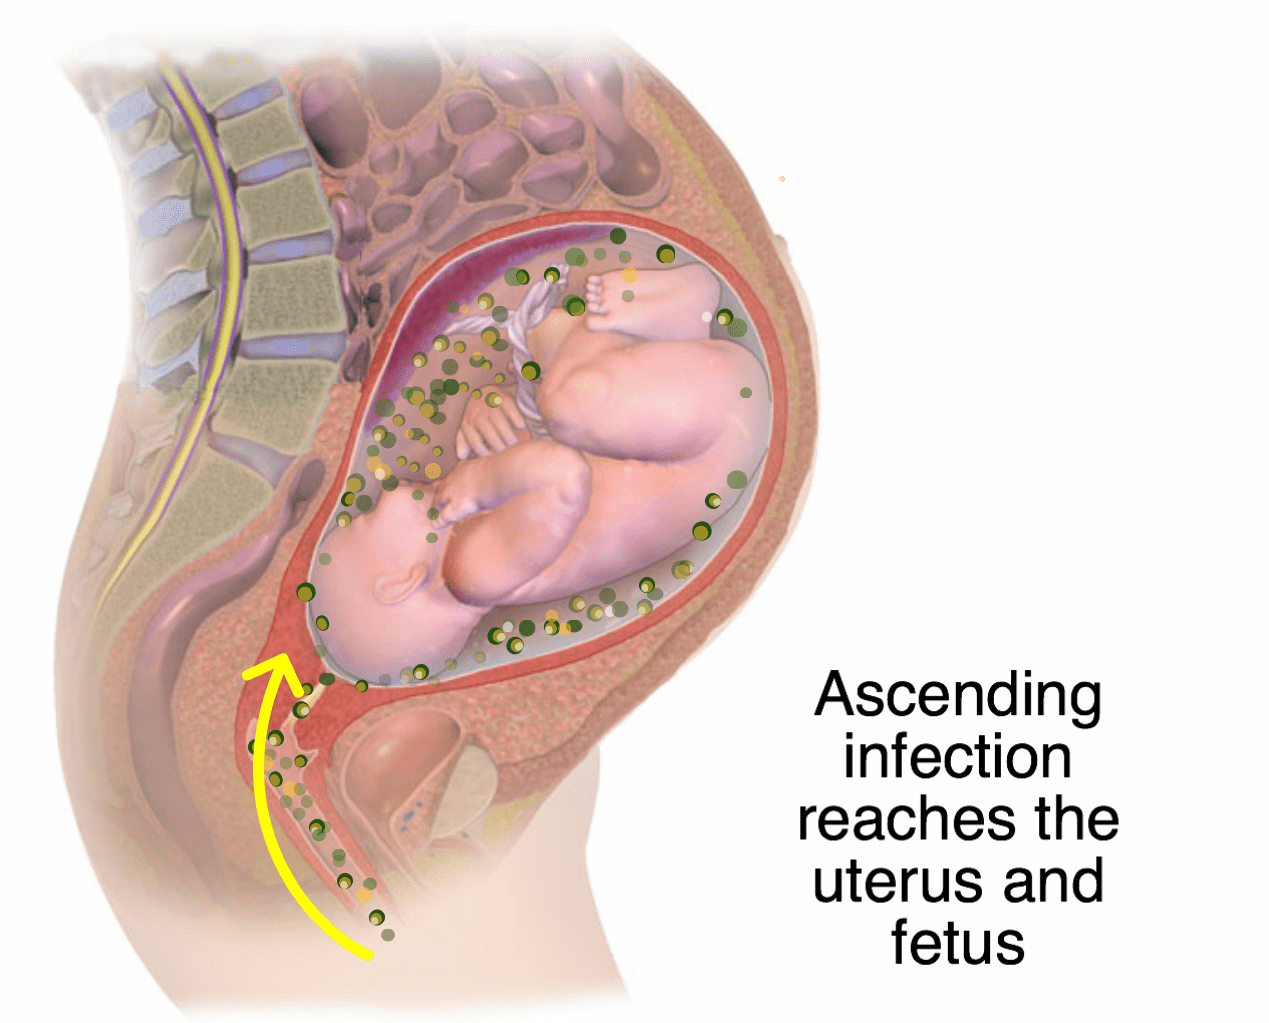

Многоводие при беременности: симптомы и лечение